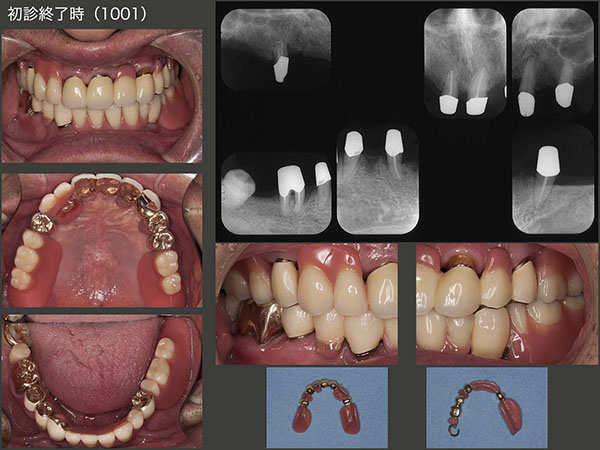

7.コーヌス義歯の無惨な経過

2007年12月初診,67歳男性.義歯が合わないとのことで来院.右側の小臼歯部のみに咬合支持があり,全体に歯周病が進行していた.著しく歯の動揺が大きい右上7および左下8は保存不可能であった.まず義歯の調整,つぎにプラークコントロールの徹底と歯周基本治療に専念した.患者さんはとても穏やかな人で,治療にも大変協力的で歯周ポケットは改善傾向を示した.

初診終了,義歯装着時の状態.コーヌス義歯は装着感が良く,とても嚙める義歯である.しかし歯科医側からみると,逆に嚙み過ぎが心配な義歯でもある.患者さんは愛着を込めて,ベンツのような義歯だとおっしゃっていた.